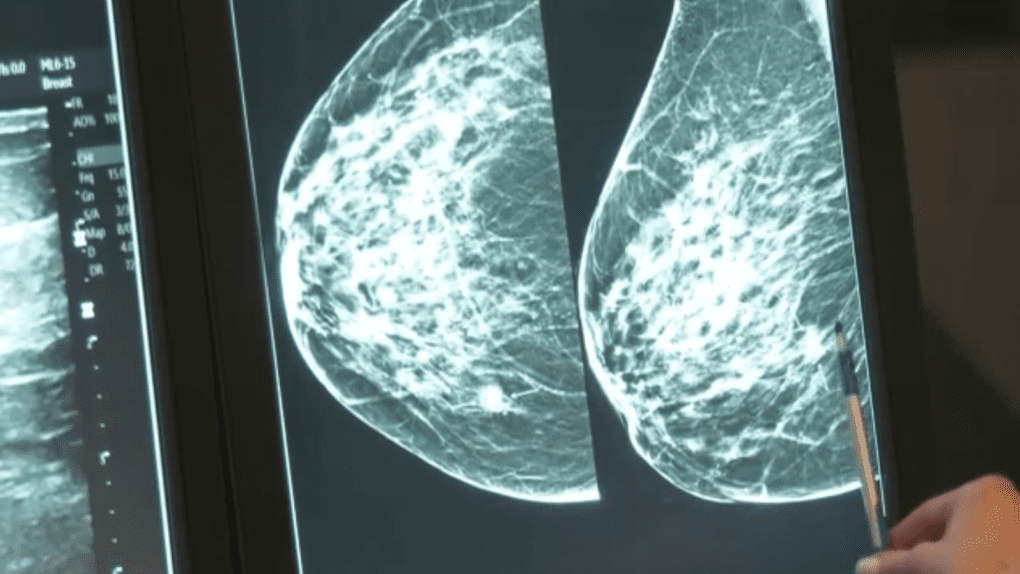

У Ванкувері радять проходити мамографію відповідно до рекомендованих інтервалів часу. Адже мамографії працюють найкраще, коли їх можна порівняти з попередніми. Це дозволяє рентгенологу зіставити їх, щоб виявити зміни у молочних залозах пацієнток. Також варто зазначити, що маммограма кожної жінки може виглядати дещо по-різному, тому що всі груди унікальні.